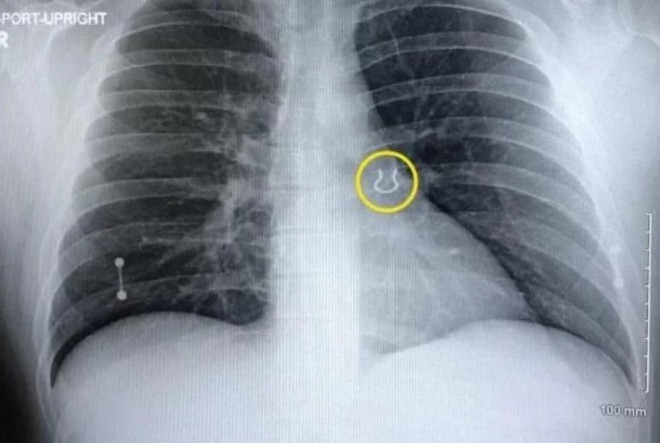

Người đàn ông tìm thấy khuyên mũi trong phổi sau 5 năm thất lạc ảnh 1Kết quả chụp X-quang cho thấy hình ảnh chiếc khuyên trong phổi của Joey. (Nguồn: Oddity Central)

Sau khi chụp X-quang, bác sĩ phát hiện có thứ gì đó bất thường nằm ở khu vực phổi trái của Joey. Kiểm tra kỹ hơn, bác sĩ cuối cùng cũng xác định được nguyên nhân.

Khi được xem hình ảnh X-quang, chính Joey cũng thấy sửng sốt. Vật khiến anh ho dữ dội cũng chính là thứ mà anh đã đánh mất nhiều năm trước đó và đã không bao giờ nghĩ rằng có thể tìm lại được nữa: một chiếc khuyên mũi.